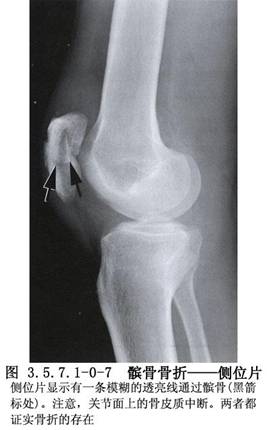

髌骨的解剖及髌骨骨折影像表现见下图(图3.5.7.1-0-1~3.5.7.1-0-10)。